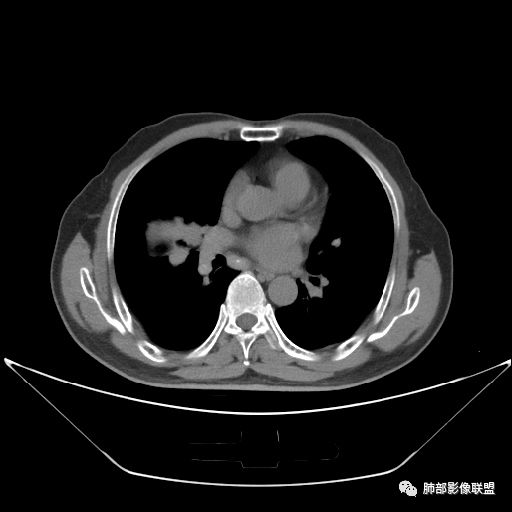

住院4天后行胸部增强CT

静脉期

老年男性,因“咳嗽咳痰1月余。”入院。病程中咳嗽咳痰,咳黄白痰,间断咯少许鲜红色痰血。PPD阳性。胸CT:右肺中叶外侧段支气管管腔阻塞,大片实性病变,病灶边缘光滑,部分边缘膨隆,可见分叶,肺门及纵隔可见肿大淋巴结,并可见钙化。增强可见病灶明显强化,而且延迟强化明显,病灶内多发低密度区,内见血管影,血管变细、部分血管破坏。考虑恶性病变可能性大,鉴别慢性肉芽肿性病变。

胸CT:跨叶大肿块,主体在中叶,右中叶外侧段支气管阻塞,病灶部分边缘膨隆,可见分叶,部分边缘平直,肺门及纵隔可见肿大淋巴结。增强病灶不均匀强化,延迟强化明显,病灶内多发低密度区,内见血管飘浮,部分血管变细、模糊。考虑:恶性病变可能性大,大细胞?淋巴瘤?鉴别慢性肉芽肿性病变。

右肺中叶软组织肿块,外围向内生长,叶间胸膜向前内移位,肿块近肺门侧跨叶,中叶外侧段支气管截断,密度不均匀,双侧肺门及隆突下见肿大淋巴结,增强后呈中度不均质强化,肺动脉供血,多发坏死区,边界尚清,坏死区域内见结构,结合病史考虑恶性,鉴别诊断1结核,爬行征是沿支气管树分布,外宽,内窄,周围有卫星灶,内气管狭窄后扩张,此例沿叶间胸膜长轴分布,气管有截断,不典型。2炎性肉芽肿,符合的地方下方层面增强后延迟性轻度环形强化,不符临床无发热等急性感染病史,实验室指标不符,病灶周围渗出及慢性炎性改变有,不明显。

吴婧老师和南边老师都对该病例进行了深入分析。从支气管管壁的增厚,支气管狭窄后扩张,支气管粘液栓,病灶形态,到病灶不均匀强化及坏死彻底,到周边病灶及肺组织空气的潴留,加之纵隔内淋巴结肿大伴钙化等等,都支持慢性炎性病灶,尤其是结核。

墨西哥仙人掌征---结核        影像上结核灶,粗大的均匀枝干,推测是支气管囊状扩张引起的,在非支气管区,形成圆形坏死囊群;如果这些坏死比较稀薄,又遇到扩张支气管,就会形成粗大的“墨西哥仙人掌”。结核引起的支气管近端炎症纤维化,可以造成支气管阻塞,从而将干酪样坏死物封堵在管腔内。仙人掌主干内部应该是干酪为主,稀薄的,具有流动性,时间久了会出现钙化。